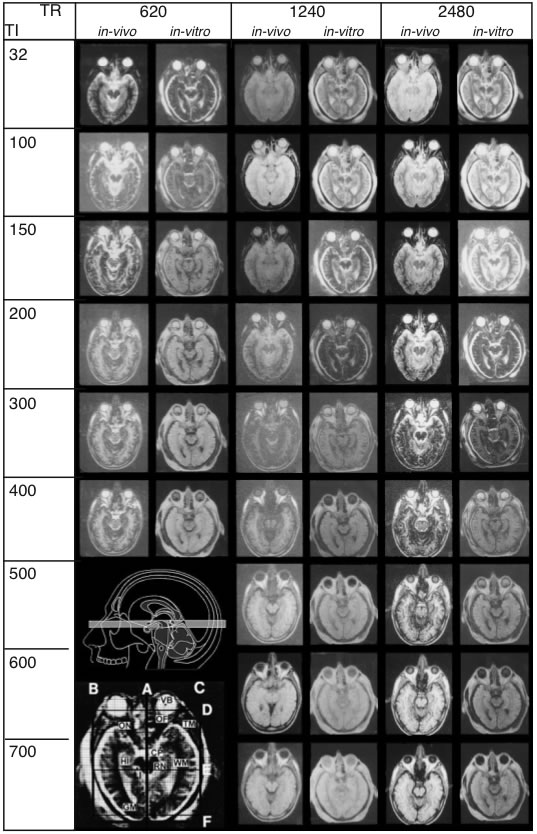

In autopsy brains, relaxation times, signal-to-noise ratio, and contrast are altered due to absence of flow effect, cessation of metabolism and fixation procedures. In order to perform comparison analysis between living and postmortem tissue, parameters that influence signal intensity were measured under both in vivo and in vitro conditions. For such a correlation, the heads of two volunteers and of two cadaver heads were scanned. The parameters of the IR and SE sequences and corresponding images of one image plane are shown in Fig. 1.

Figure 1 – A

Sequence parameters used for in vivo/in vitro

correlation. Measurements shown were taken from a

25-year-old volunteer (in vivo) and from a cadaver head

(in vitro). A: TR (repetition time) and TI (spin-lattice relaxation) times for IR sequences

Figure 1 – B

TR and TE (spin-spin relaxation) times for SE sequences. MR images obtai

ned under in vivo and in vitroconditions exhibit striking

differences. Upper inset (A) shows the plane of sectioning. The lower inset shows every scan overlayed with

a grid (A-F) to secure precise location of the same regions of interest throughout the series. (Abbreviations:

CP: cerebral peduncle, GM: gray substance), Hi: hippocampus, Li: cerebrospinal fluid, OF: orbital fat, ON: optic

nerve, RN: red nucleus, TM: temporalis muscle, VB: vitreous body, WM: white matter.